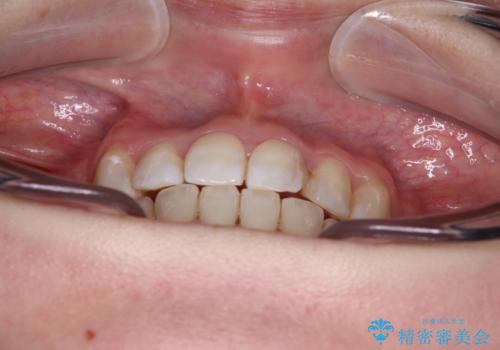

八重歯のためずれていた上下の正中をほぼ一致する位置に整えることができました。

重なって汚れの溜まりやすかった部分も改善され、大変満足していただけました。